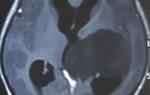

Bệnh nhân đến thăm khám tại Bệnh viện Đa khoa Quốc tế Nam Sài Gòn trong trạng thái đau đầu liên tục. Thời gian gần trước khi nhập viện bệnh nhân có xuất hiện các triệu chứng như nhức đầu, chóng mặt, tê chân, đi đứng không vững. Kết quả chụp cắt lớp não (CT scanner sọ não), chụp cộng hưởng từ não (MRI) phát hiện có khối u choán chỗ tiểu não vùng hố sau bên trái. Các bác sĩ chẩn đoán bệnh nhân bị u não thất IV.

ThS.BS.CKII Đỗ Anh Vũ - người trực tiếp thực hiện ca phẫu thuật cho biết, đây là khối u nằm ở vị trí khó tiếp cận, gần với các cấu trúc mạch máu thần kinh quan trọng, cũng như có nhiều mạch máu nuôi u nên việc điều trị cho bệnh nhân để bóc tách lấy toàn bộ khối u là không dễ dàng.

Tuy khối u có kích thước nhỏ nhưng vùng hố sau của não, xung quanh u có nhiều chức năng quan trọng, đòi hỏi phẫu thuật viên phải thao tác vô cùng khéo léo để tránh gây ra tổn thương mô não ở vùng này nhằm hạn chế tối đa khả năng bệnh nhân tử vong hay chịu những di chứng sau phẫu thuật.